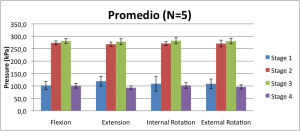

Tesis Doctoral

Estudio de presión articular de cadera, Influencia de la lesión del rodete acetabular.

El estudio muestra cómo la reparación del rodete acetabular logra restaurar las presiones articulares previas a la lesión del mismo